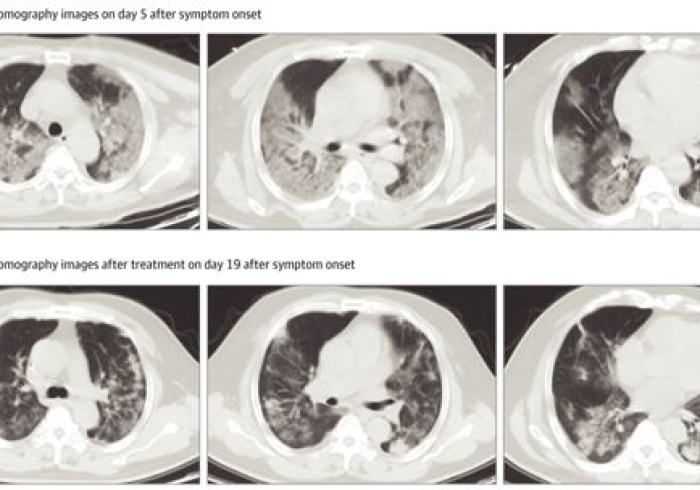

症状差异新型冠状病毒感染的症状具有多样性和潜在严重性:典型症状包括发热、干咳、乏力,部分患者可出现呼吸困难、嗅觉或味觉丧失;重症患者可能发展为急性呼吸窘迫综合征(ARDS)、多器官功能衰竭等。